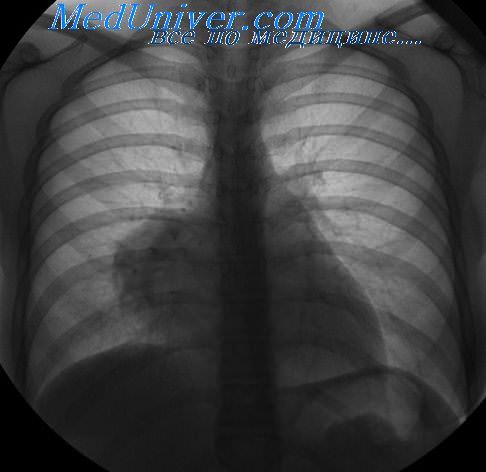

Рентгеновские снимки тератомы средостения: Диагностика и лечение

Раздел: Фотоэссе